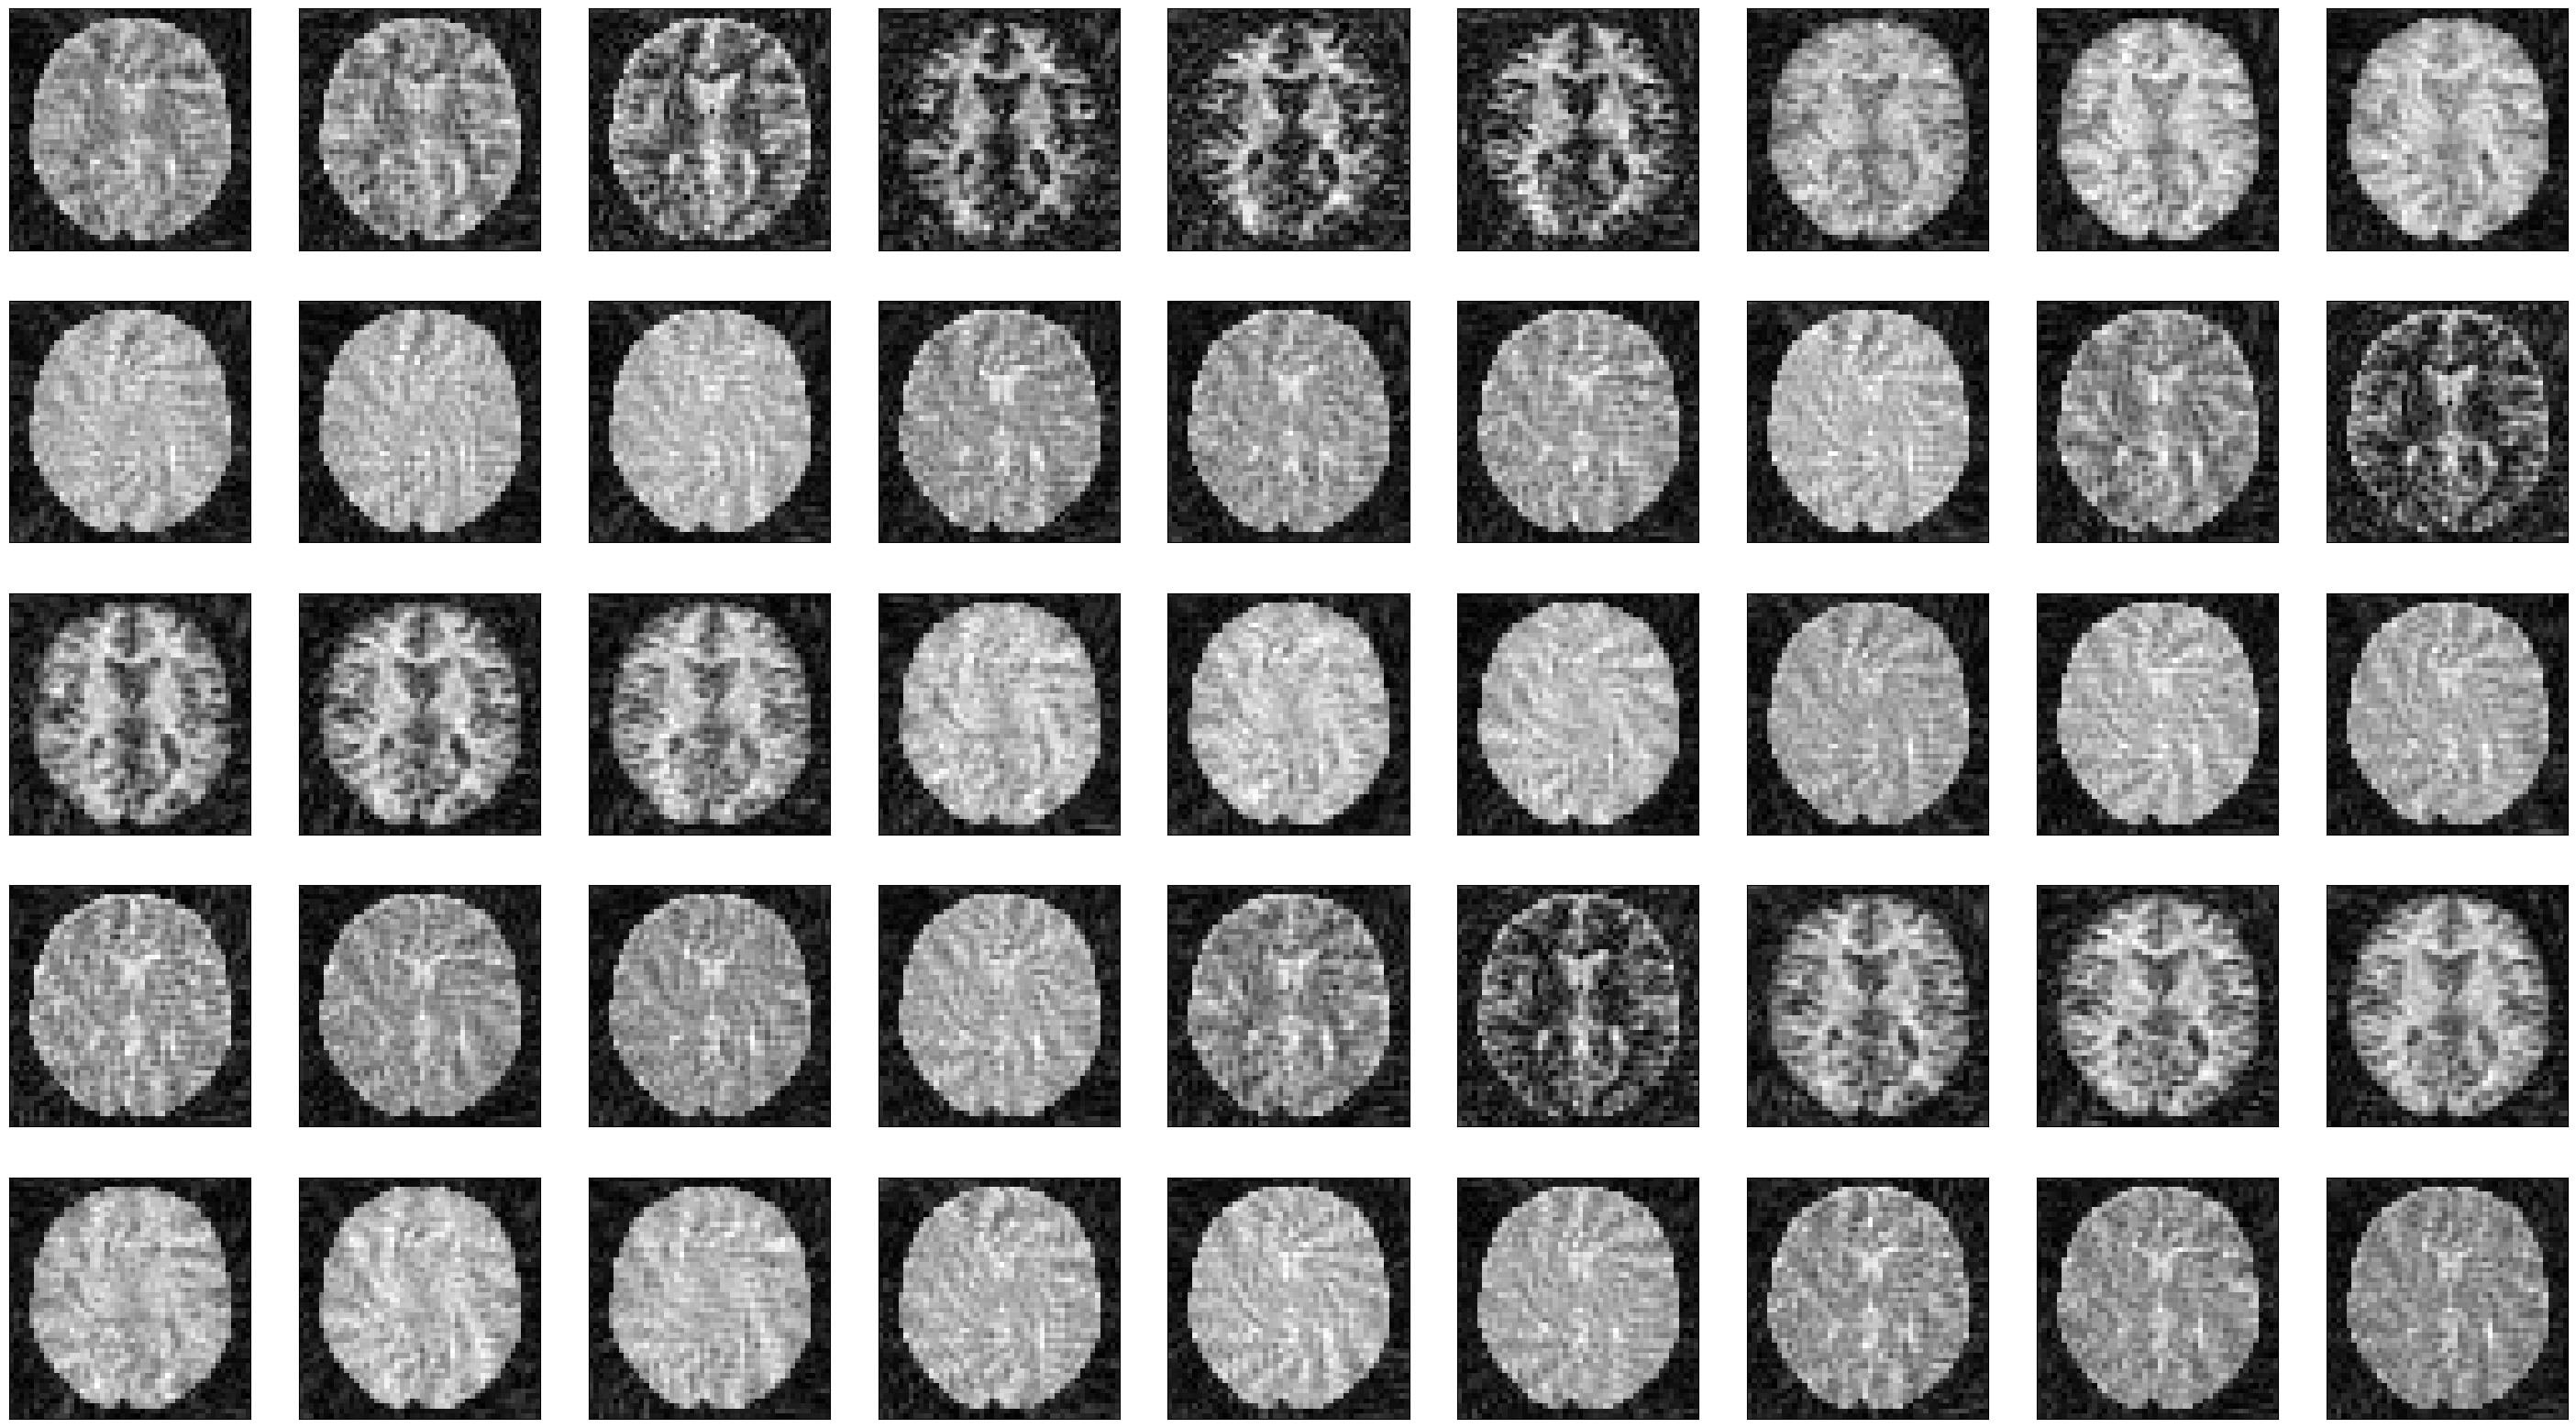

We can now plot the images at different time points along the acquisition.

idat = idata.data.abs().numpy().squeeze()

fig, ax = plt.subplots(5, idat.shape[0] // 5, figsize=(4 * idata.shape[0] // 5, 5 * 4))

ax = ax.flatten()

for i in range(idat.shape[0]):

ax[i].imshow(idat[i, :, :], cmap='gray')

ax[i].set_xticks([])

ax[i].set_yticks([])

_images/402573d4446fa2ab89d8636db8ca4cabf5cdc92bb2cffd28d0b1b2f26debd2a7.png